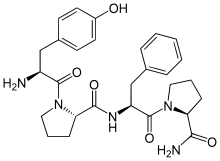

| Opioid peptides | Skeletal molecular images |

| Adrenorphin |  |

| Amidorphin |  |

| Casomorphin | |

| DADLE | |

| DAMGO |  |

| Dermorphin | |

| Endomorphin |  |

| Morphiceptin |  |

| Nociceptin |  |

| Octreotide |  |

| Opiorphin |  |

| TRIMU 5 |  |